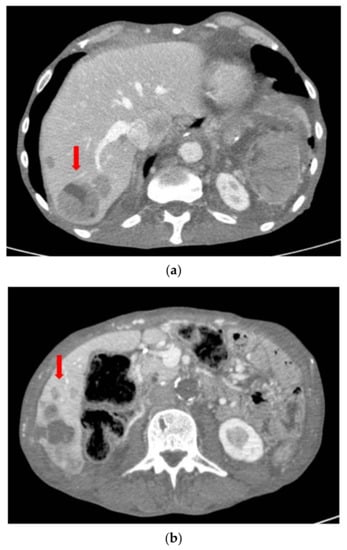

2. Case Report